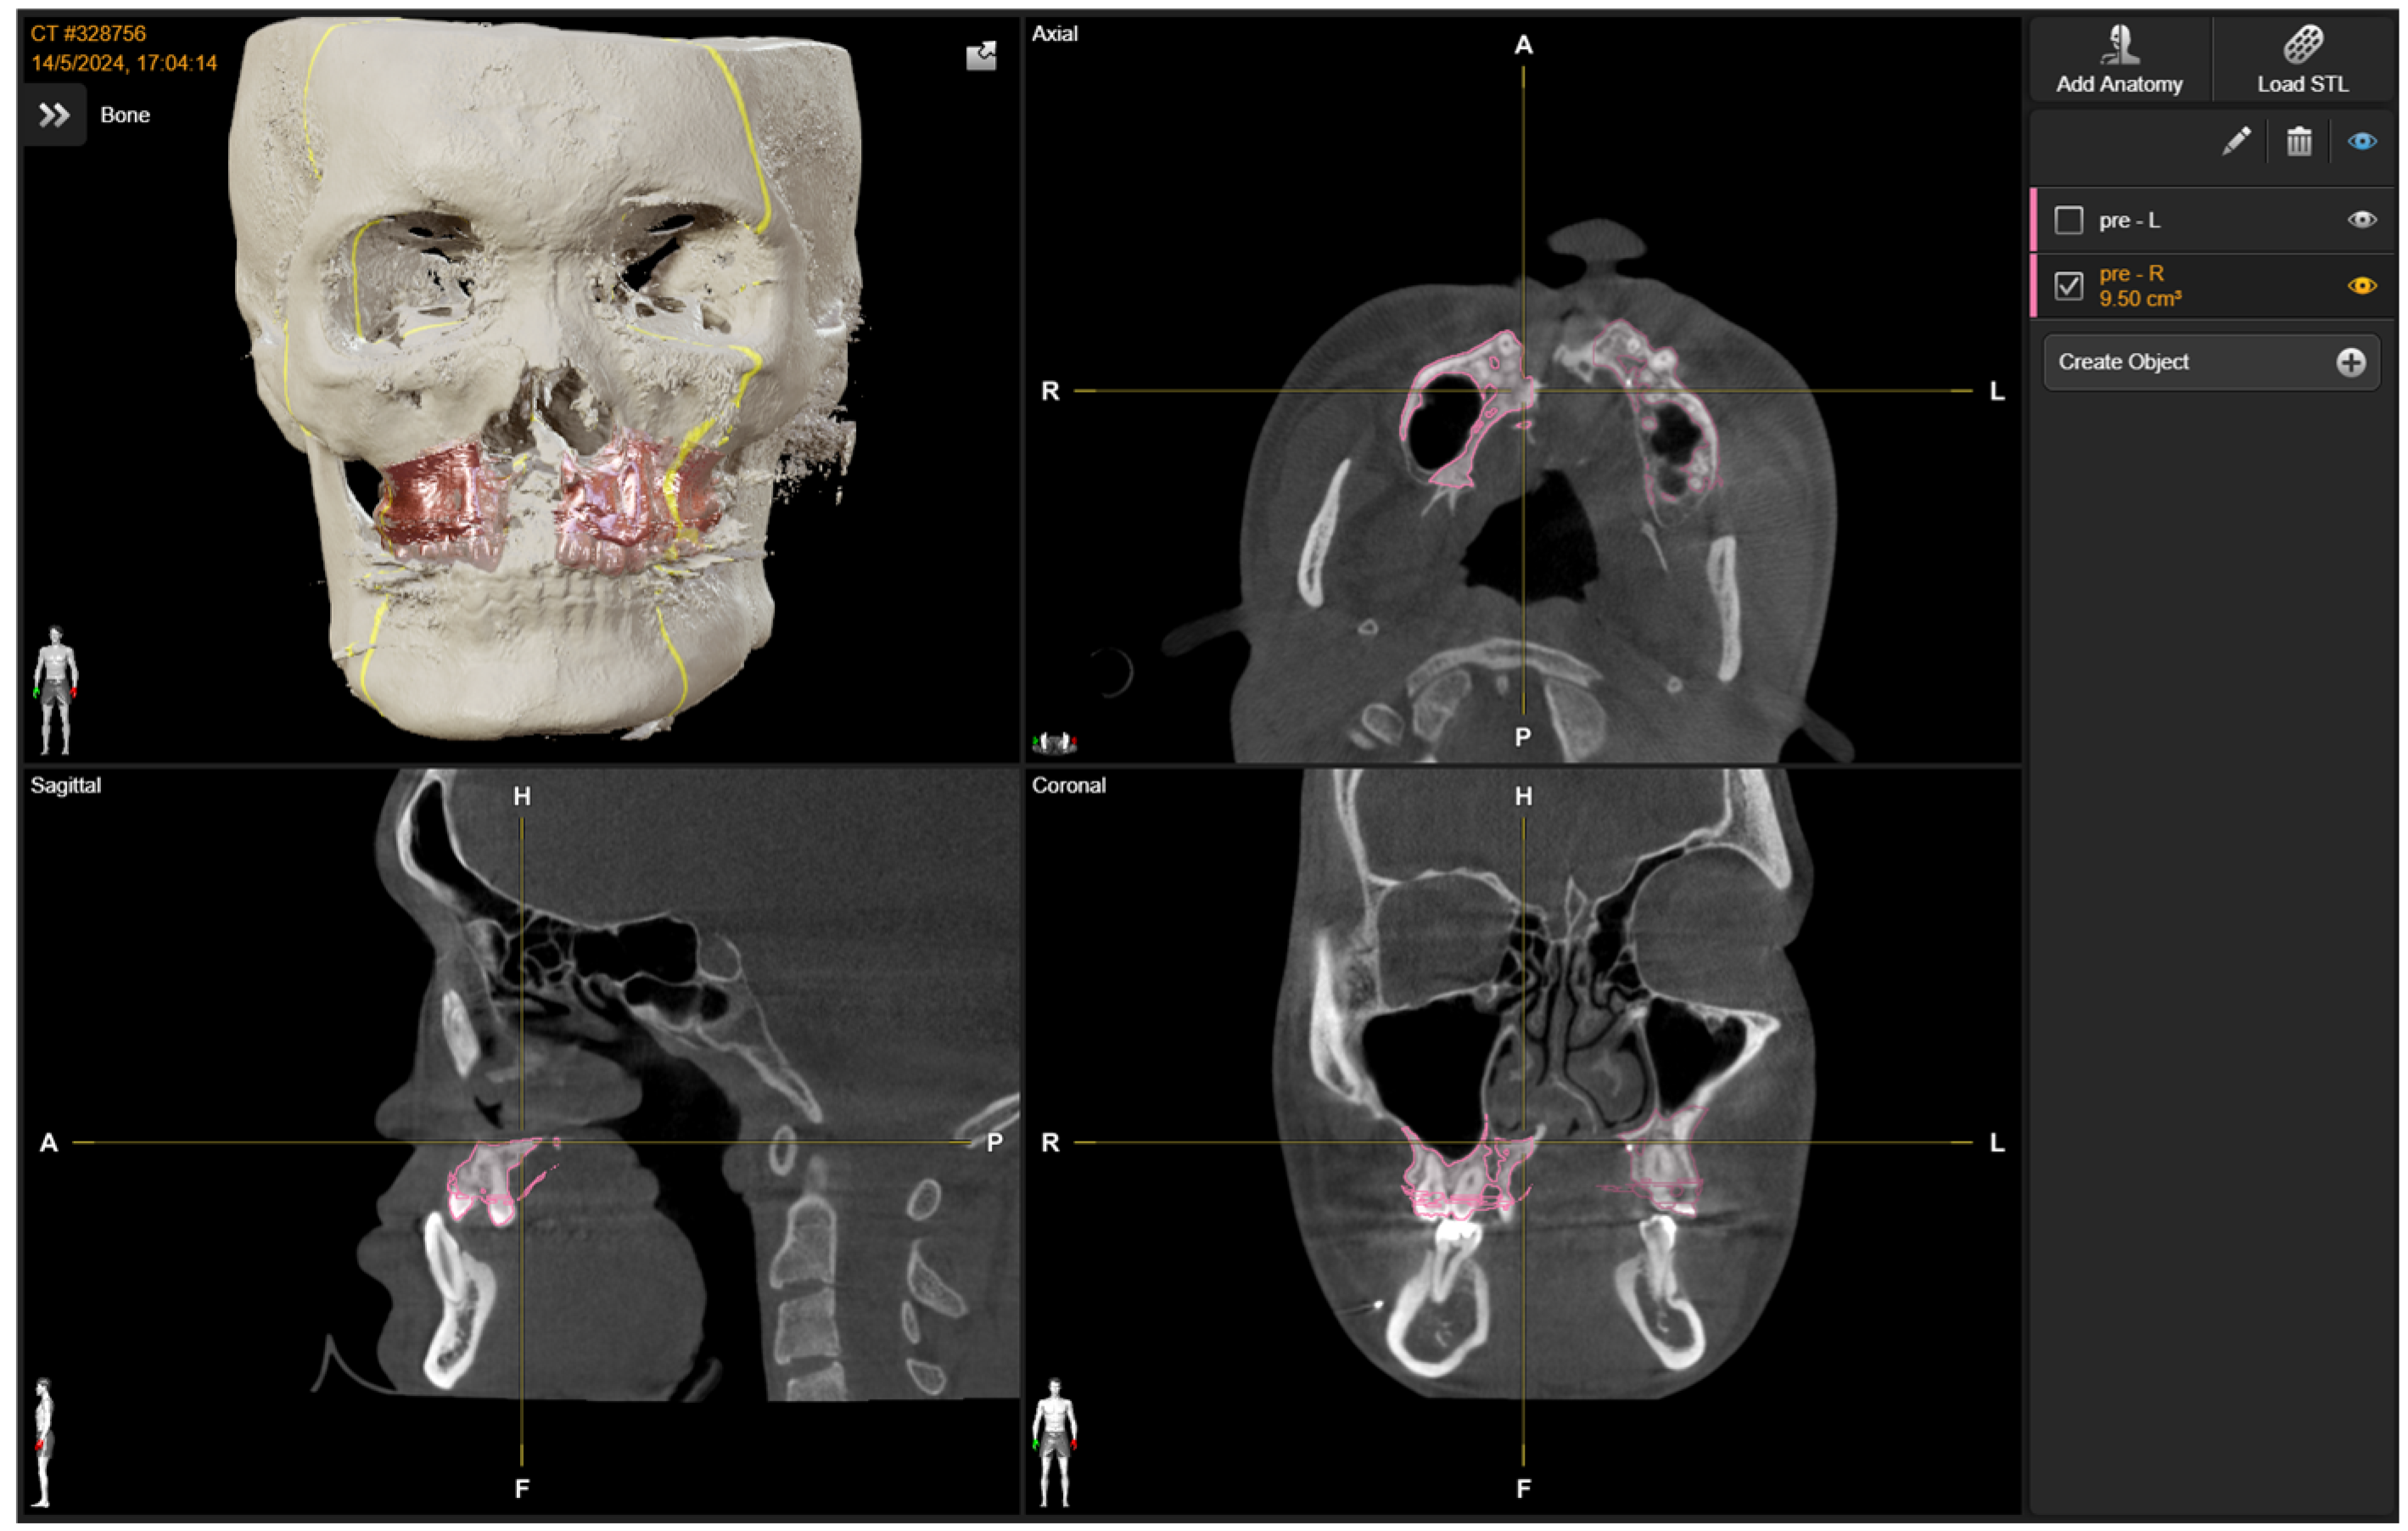

2. Materials and Methods

2.1. Preoperative Planning

2.2. Intra-Operative Navigation

3. Results